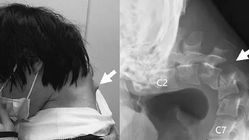

Seorang pasien pria asal Jepang berumur 25 tahun, yang biasanya banyak waktu luangnya digunakan untuk memainkan telepon genggamnya, kini menghadapi masalah serius. Ia memiliki benjolan besar di area belakang leher yang semakin membengkak, sehingga membuatnya tak bisa lagi menegakkan kepala hanya dengan menggunakan otot pada lehernya.

Menghabiskan waktu berjam-jam sambil menundukkan leher ke arah ponsel sehingga membentuk benjolan besar di area belakang lehernya.

Pemindaian mengungkapkan adanya perubahan bentuk pada tulang leher bagian bawah serta dislokasinya, sementara itu juga ditemukan ada pembentukan jaringan parut di area tulang punggung atas karena sudah ‘terlalu lama’ berada dalam posisi tertarik tersebut.

Dengan melalui berbagai tahap operasi bedah, tim medis menyingkirkan bagian dari tulang belakang yang bengkok serta jaringan parut sebelum menyuntikkan sekrup dan batangan logam ke dalam area leher mereka guna meningkatkan posisi badannya.